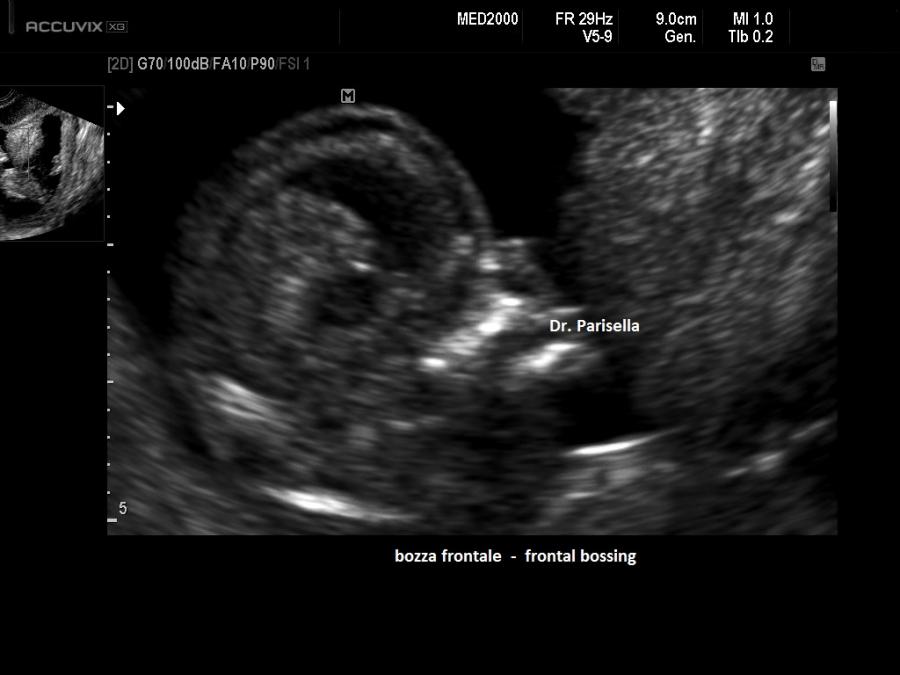

• anomalie cranio-facciali (macrocrania con bozze frontali prominenti, fronte alta e larga, naso a sella, ipertelorismo).

2. anomalie facciali (bozze frontali, ipertelorismo, naso a sella),